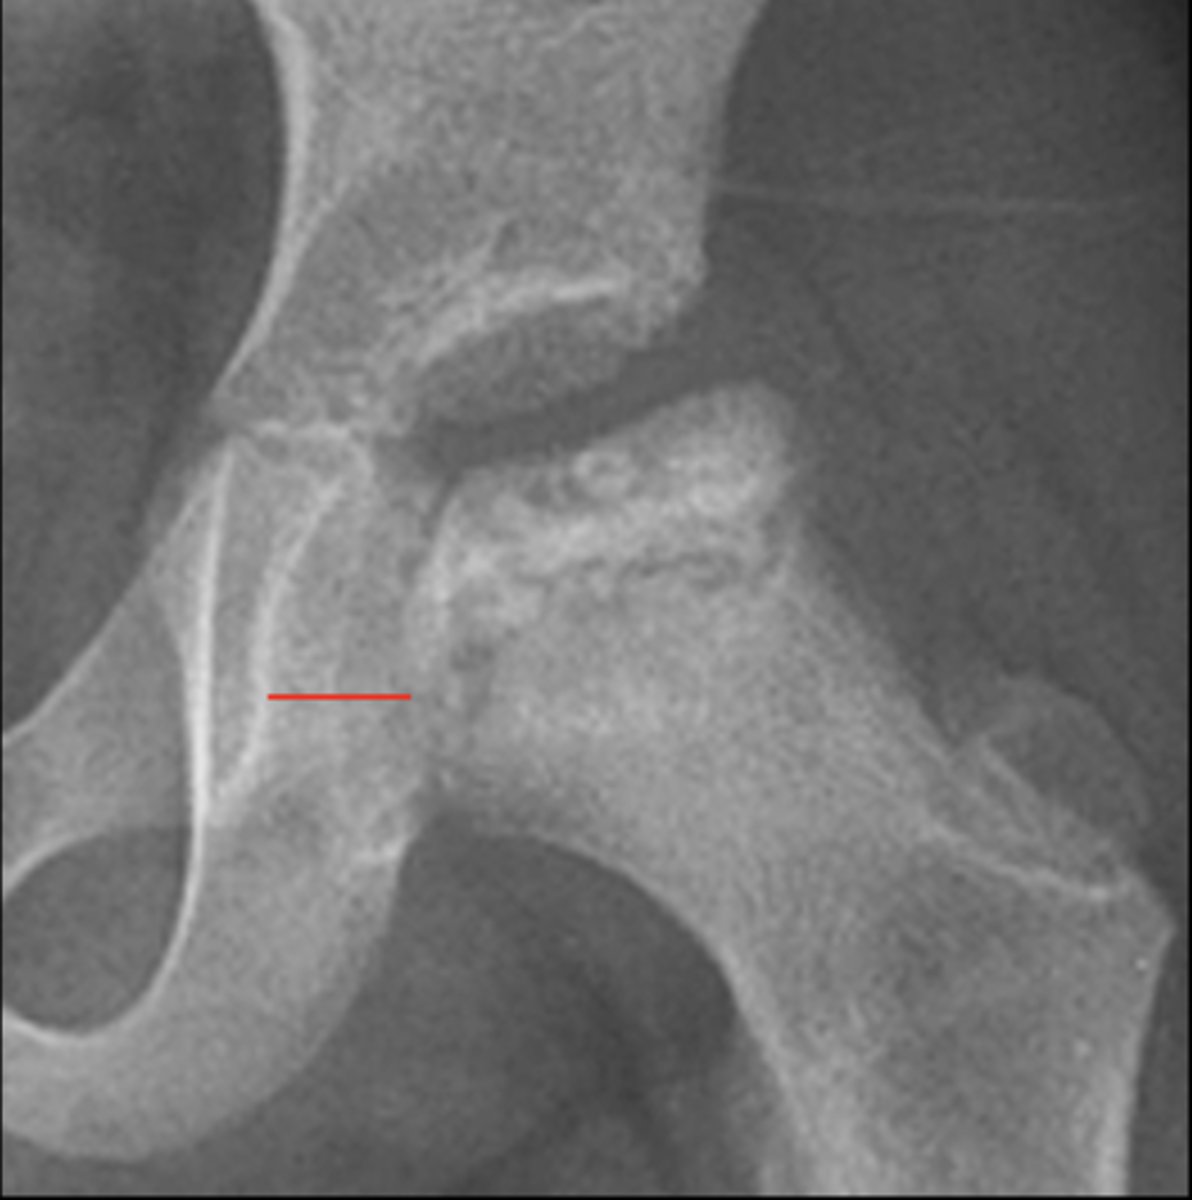

Kohler's teardrop distance

ID measurement line

<p>ID measurement line</p>

- AP pelvis

- AP hip

What views are needed to see Kohler's teardrop distance?

<p>What views are needed to see Kohler's teardrop distance?</p>

- Medial margin of femoral head

- Lateral border of teardrop

Kohler's teardrop distance landmarks

<p>Kohler's teardrop distance landmarks</p>

6-11 mm

Normal Kohler's teardrop distance measurement

<p>Normal Kohler's teardrop distance measurement</p>

2 mm

The normal Kohler's teardrop distance is 6-11 mm, and there should be no greater than a _____ difference when comparing to the contralateral side

<p>The normal Kohler's teardrop distance is 6-11 mm, and there should be no greater than a _____ difference when comparing to the contralateral side</p>

Hip joint effusion

Clinical significance of an enlarged Kohler's teardrop distance

<p>Clinical significance of an enlarged Kohler's teardrop distance</p>

Waldenstrom's sign

What sign indicates an enlarged Kohler's teardrop distance?

- Accentutation of the normal limits

<p>What sign indicates an enlarged Kohler's teardrop distance?</p><p>- Accentutation of the normal limits</p>

Intracapsular swelling/joint effusion

Waldenstrom's sign is usually an indication of _____

<p>Waldenstrom's sign is usually an indication of _____</p>

Inflammatory arthritis

Clinical significance of a small Kohler's teardrop distance

<p>Clinical significance of a small Kohler's teardrop distance</p>